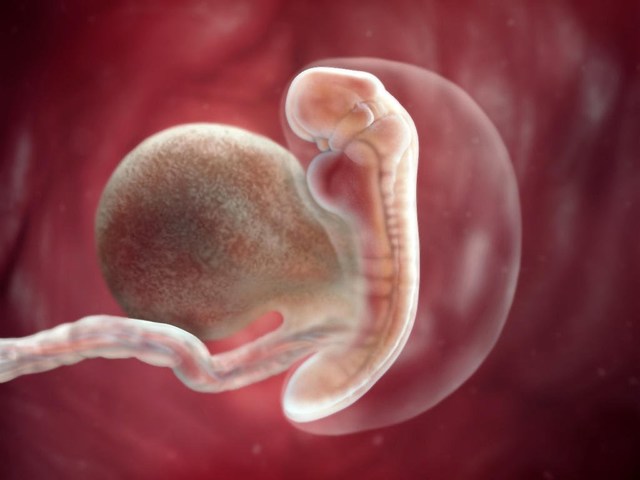

• Semana 2

Semana 2

-El embrión poco a poco toma forma.

-Se forma cerebro y tubo neural

• Semana 3

Semana 3

-Las células sanguíneas empiezan a circular en el embrión.

-El embrión cuenta ya con SN.